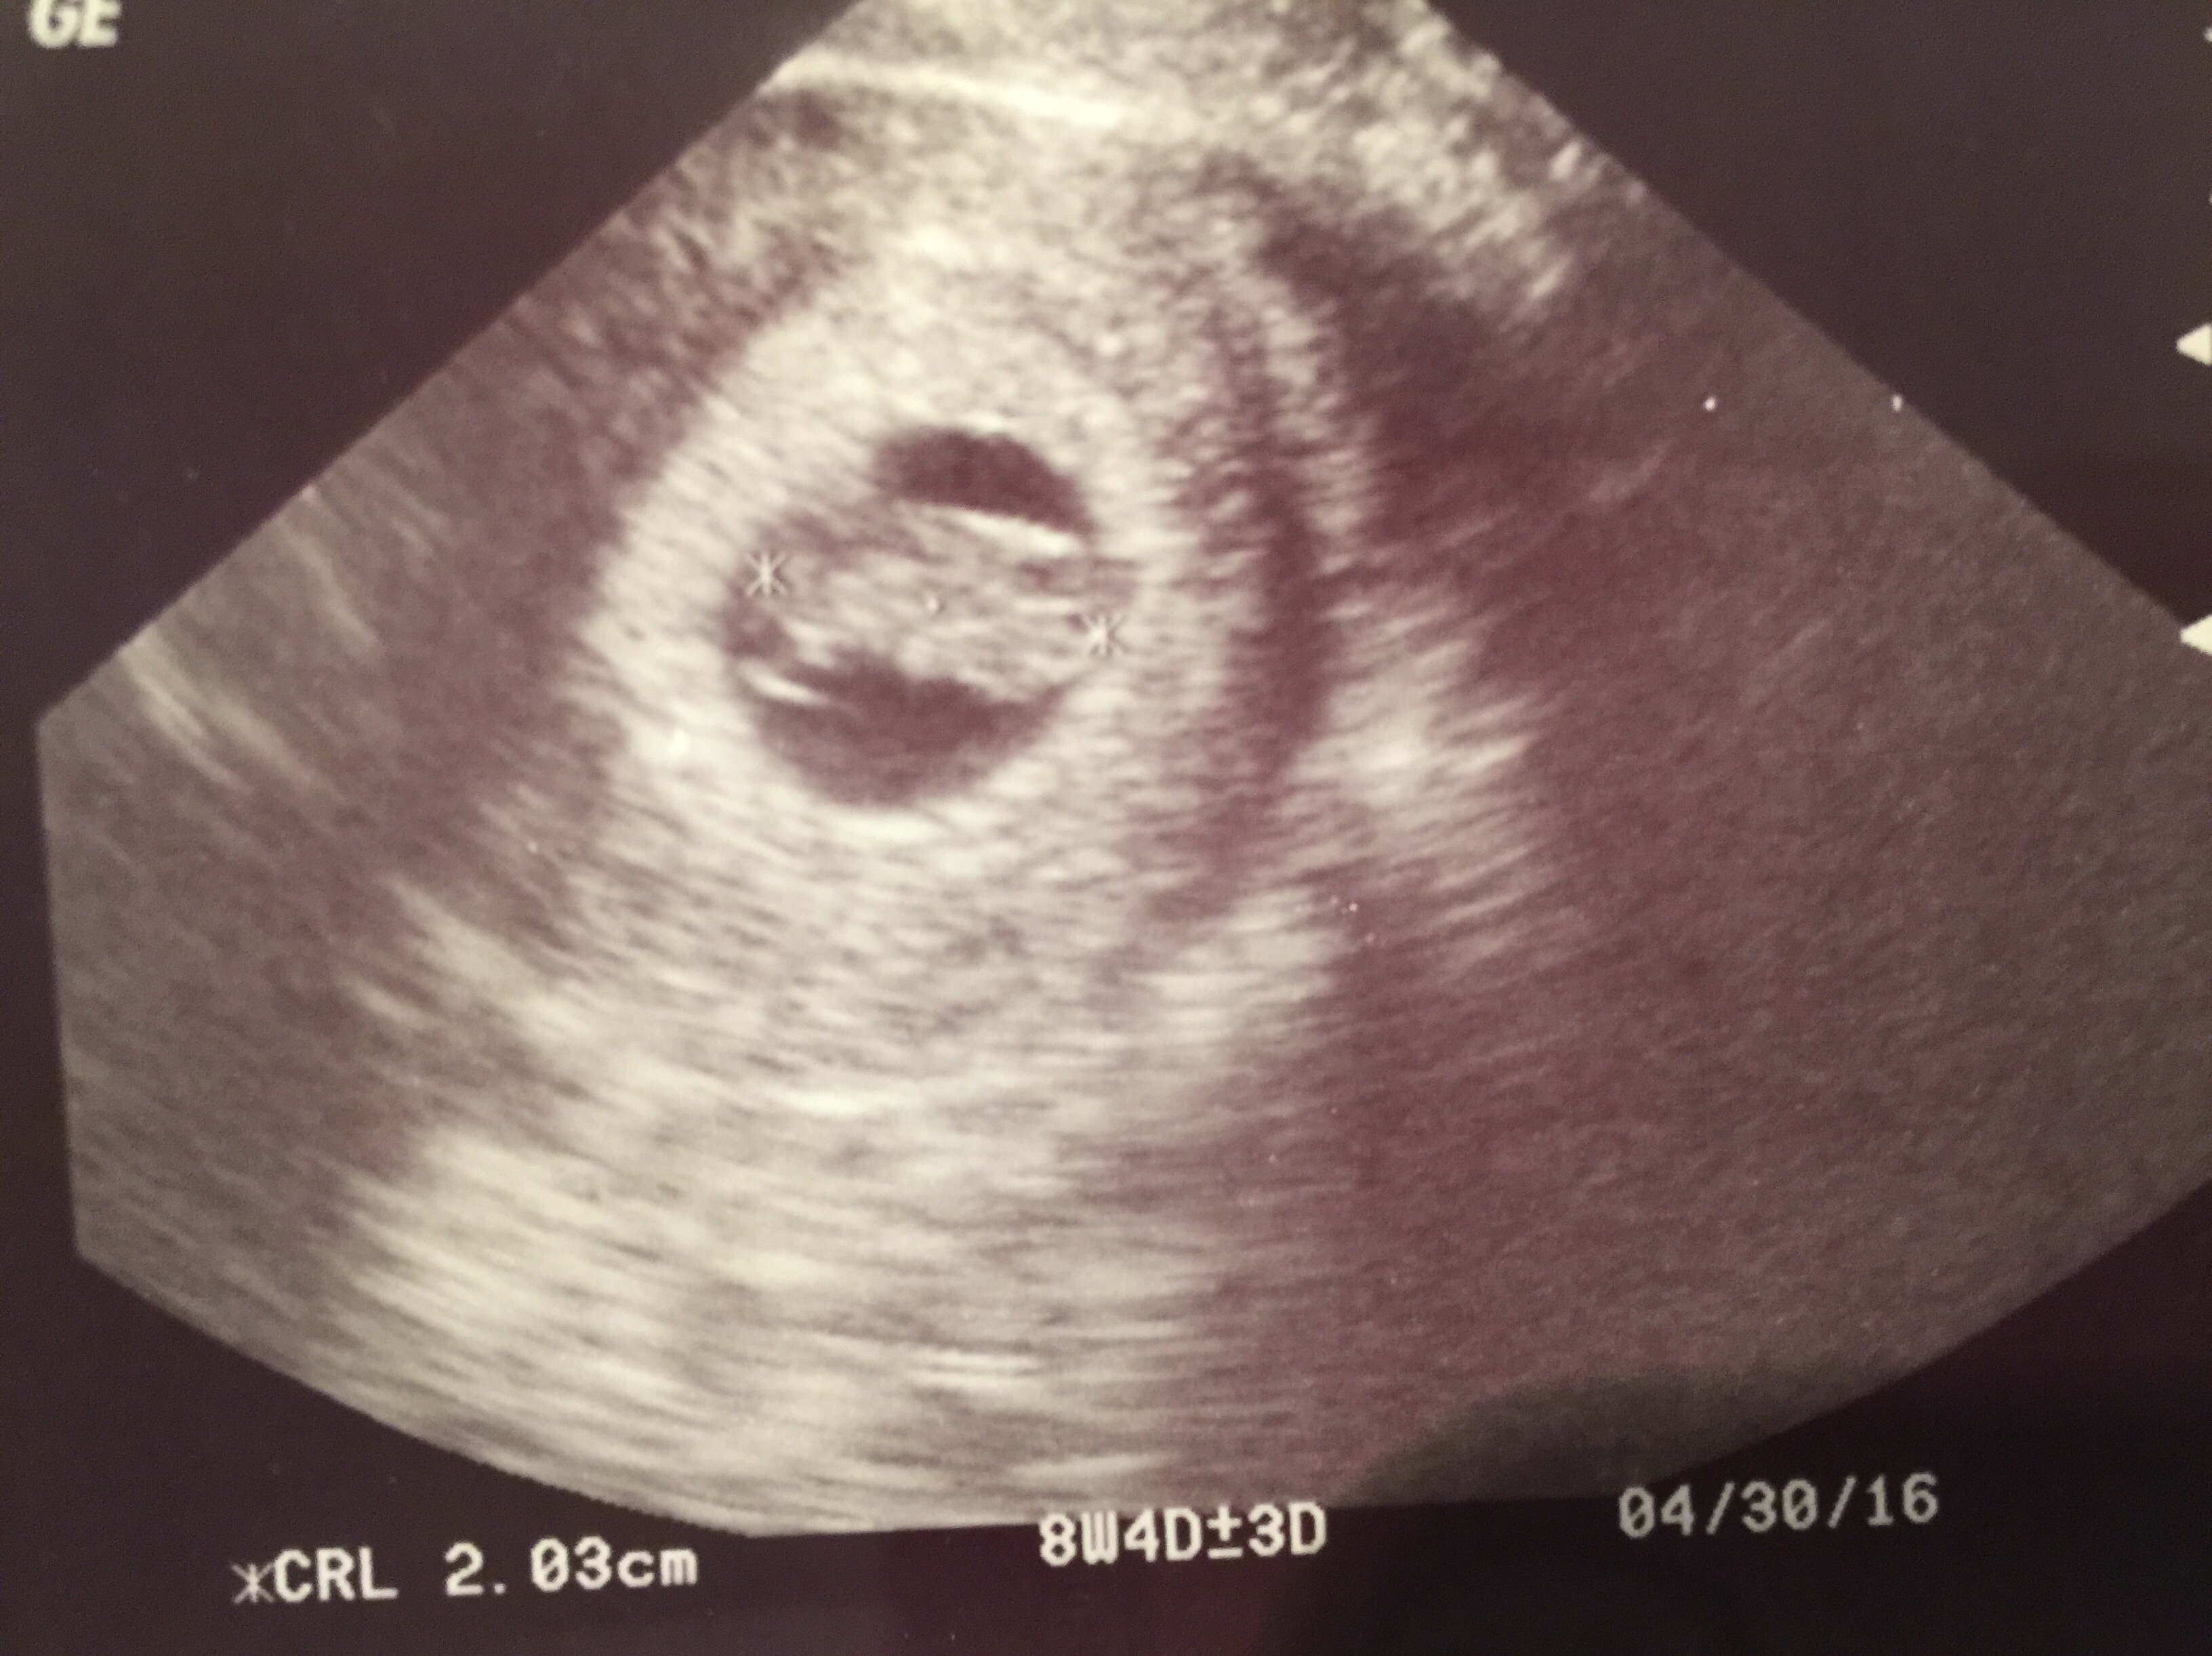

We had our first US yesterday and measured exactly as expected at 8w4d. Heart rate was 170bpm, and such a welcome sight and a relief. We were so excited to get our first peek at baby #3....even if baby does look like a turtle in the US haha!